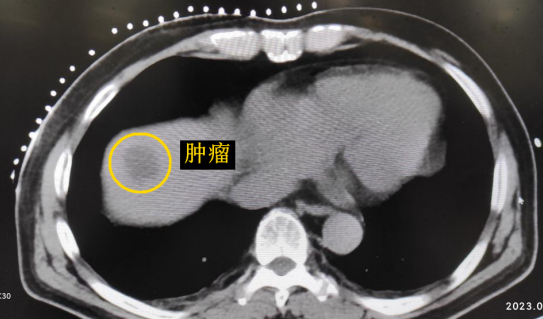

患者老年男性,曾于2021年行結(jié)腸癌手術(shù)。幾月前,發(fā)現(xiàn)肝臟轉(zhuǎn)移瘤,但沒(méi)有干預(yù)。近期CT顯示該轉(zhuǎn)移瘤明顯增大,并發(fā)現(xiàn)另一處轉(zhuǎn)移灶。

影像診療科陳寶瑩主任團(tuán)隊(duì)評(píng)估后指出,較大的腫瘤位于肝頂部緊貼膈肌,如果繼續(xù)發(fā)展,腫瘤很可能突破肝包膜侵犯到膈肌,建議及時(shí)干預(yù)。病變緊臨膈肌,如果要完全消融,膈肌損傷的可能性就比較大,與其他局部治療方式比較,冷凍消融對(duì)周圍臟器、血管及神經(jīng)損傷的可能性較小、安全性更高、患者疼痛感較輕,建議通過(guò)CT精準(zhǔn)引導(dǎo)下經(jīng)皮微創(chuàng)冷凍消融治療。

CT精準(zhǔn)定位腫瘤